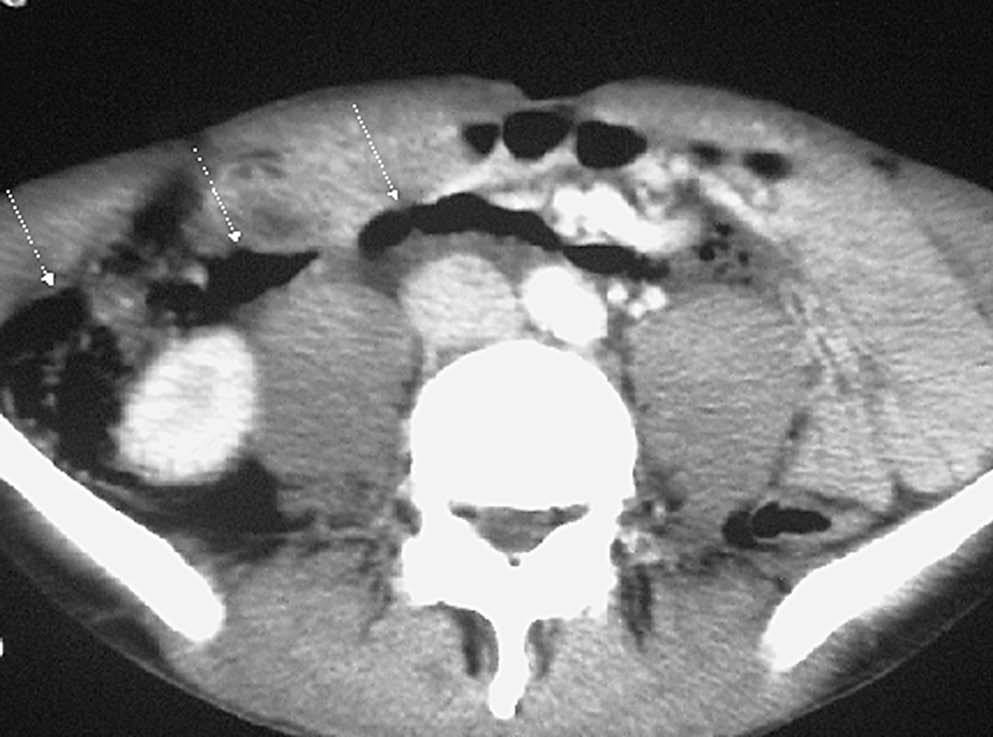

La lesión duodenal por traumatismo es rara y es la tercera porción del duodeno la que con más frecuencia se lesiona al ser comprimida contra la columna. Se puede producir contusión o perforación, observándose en ambas situaciones engrosamiento de la pared duodenal, borrosidad de la grasa periduodenal o líquido en el espacio pararrenal anterior derecho. En caso de contusión se puede identificar el hematoma como una colección de densidad intermedia o alta que comprime la luz duodenal en la TC. Signos de perforación son la presencia de aire adyacente al duodeno retroperitoneal (fig. 3) o la extravasación de contraste oral al retroperitoneo9,10.

Fig. 3--Perforación duodenal traumática. Estudio de tomografía computarizada que muestra aire en retroperitoneo (flecha) tras traumatismo.